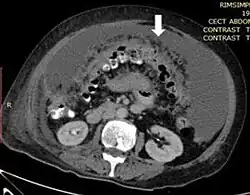

medical image showing thickened greater omentum

Axial abdominal computed tomography featuring omental caking due to peritoneal carcinomatosis

Due to the variety of symptoms experienced by patients with omental caking,[5] omental cakes are most frequently discovered on abdominal computed tomography (CT) or ultrasound. Plain film radiography (X-ray) is not a suggested modality for investigating the spread of cancerous cells in the abdomen due to the poor spatial resolution amongst soft-tissue densities. Contrast resolution obtained through CT allows radiologists to investigate omental caking for morphology, intraperitoneal fluid, and regional lymphadenopathy assists in proper diagnosis so clinicians, surgeons, and oncologists can plan the appropriate course of treatment.[8]